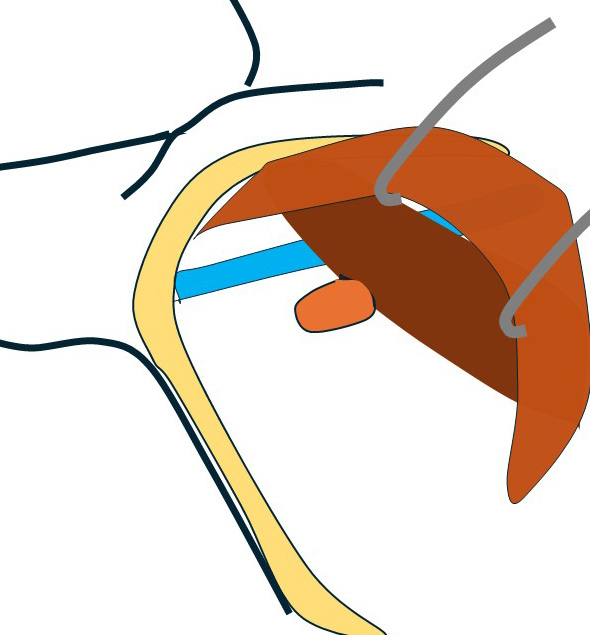

大きなリンパ節(左図 黄色)をこの視野で腋窩静脈から外していったが一部は(小胸筋裏を超えて)その奥のリンパ節に連続しており、この視野から(この大きなリンパ節を)外すことは断念して(レベルⅢ郭清の際に)外す方針とした。

4.鎖骨下郭清(レベルⅢ)

ここで(引っ張り上げていた)小胸筋を元に戻し大胸筋のみ筋鈎で思いっきり内側へ引き小胸筋全面(奥まで)直視下とした。

この部分の拡大図

小胸筋内側(奥)は膜で連続しておりその奥は見えない。

鎖骨下静脈はこの膜で視認できないため、これの損傷を防ぐために、小胸筋裏に指を入れこの静脈の走行を確認しつつ、それより尾側で小胸筋膜を小胸筋に沿って切離し貫通した。

この膜が切離された部分にテープを入れて、小胸筋を手前(外側)に思いっきりけん引した。

これにより先に途中まで外していた大きなレベルⅡリンパ節(図の黄色)とそれに連続していたレベルⅢ(図の赤色)が鎖骨下静脈とともに直視下となり、慎重に小血管を処理しながら鎖骨下静脈から外して郭清。

このまま鎖骨下静脈及び胸壁からバイクランプでレベルⅢ群を全て郭清した。